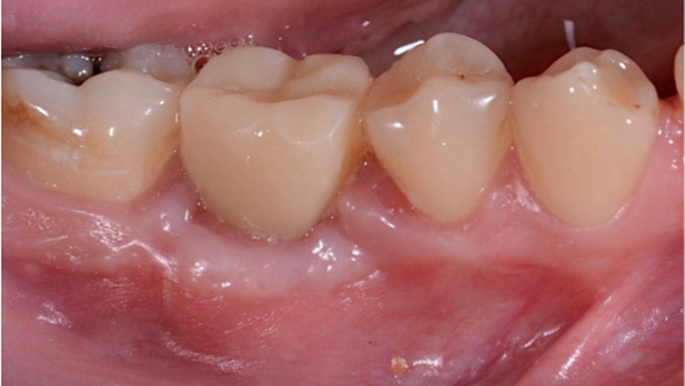

Clinical case: Delayed implant placement: sinus floor elevation by means of lateral

approach & implant placement with GBR

- Courtesy of Dr. Irfan Abas, Netherlands -